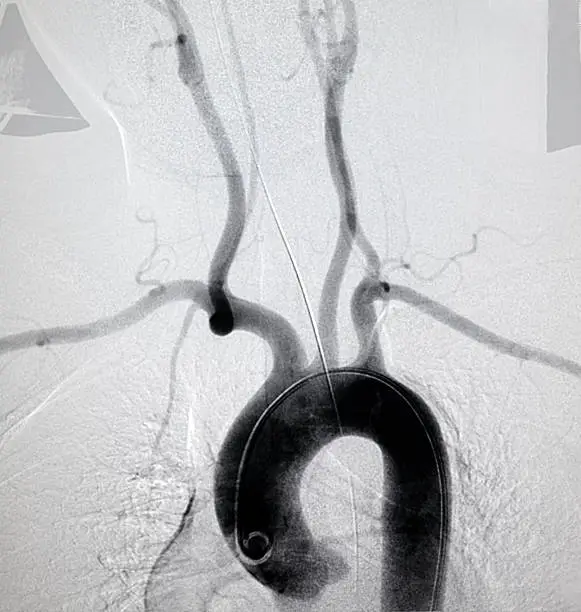

대동맥 질환

대동맥 질환은 심혈관 조영술을 통해 확인할 수 있는 또 다른 중요한 질환입니다. 대동맥은 심장에서 몸 전체로 혈액을 공급하는 주요 동맥으로, 대동맥의 기능 장애는 매우 위험한 상태를 초래할 수 있습니다. 대동맥 질환에는 대동맥류, 대동맥 박리 등이 포함되며, 조영술을 통해 이러한 질환을 정확히 진단하고 적절한 치료를 결정할 수 있습니다.

대동맥류는 대동맥이 비정상적으로 확장되는 상태를 의미하며, 이는 대동맥 벽의 약화로 인해 발생합니다. 대동맥류가 파열되면 생명을 위협하는 상황이 초래되기 때문에, 조기 진단과 관리가 매우 중요합니다. 심혈관 조영술을 통해 대동맥의 확장 정도와 위치를 확인할 수 있으며, 이를 바탕으로 수술 여부를 결정할 수 있습니다. 조영술은 대동맥류 외에도 대동맥 박리와 같은 질환을 진단하는 데 중요한 역할을 합니다.

대동맥 박리는 대동맥 벽이 찢어져 혈액이 대동맥 벽 사이로 새어 나가는 상태로, 이는 즉각적인 치료가 필요한 응급 상황입니다. 대동맥 박리는 심한 가슴 통증을 동반하며, 조영술을 통해 박리의 정확한 위치와 범위를 확인할 수 있습니다. 이로써 신속한 수술이나 기타 치료가 결정되며, 환자의 생명을 구하는 데 중요한 검사로 작용합니다.